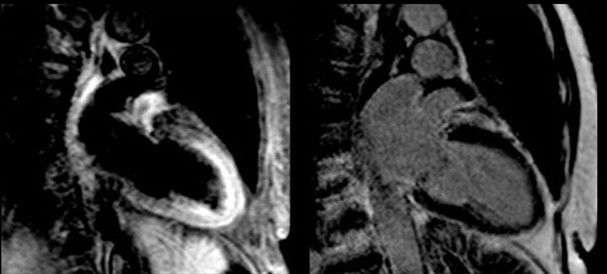

心脏收缩动态磁共振成像(MRI)显示了一名81岁TCM患者典型的心尖气球样扩张(A)。同一患者的心血管MRI(CMRI)T 2(横向弛豫时间)像显示心尖心肌T2信号强度升高[橙色](B)。这两个两腔位图像是在最初诊断TCM后3天获取的,患者在全身发作后出现短暂的心电图(ECG)改变和肌钙蛋白水平升高。

图像显示了81岁TCM患者发病3天后的两腔CMRI影像(幻灯片3是同一患者)。

左图:传统T2加权短时间反转恢复序列(STIR)快速自旋回波图像,可见心肌心尖信号强度增加,难以与缓流时管腔内血流信号进行区分。

右图:LGE 图像排除心肌瘢痕。